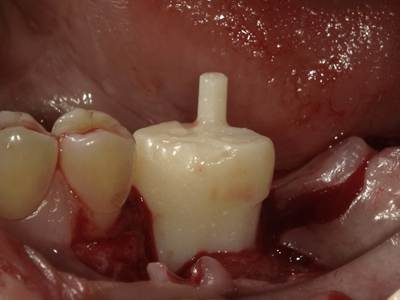

移植歯レプリカの試適(移植床の適合確認):症例1-2

左下6番抜歯